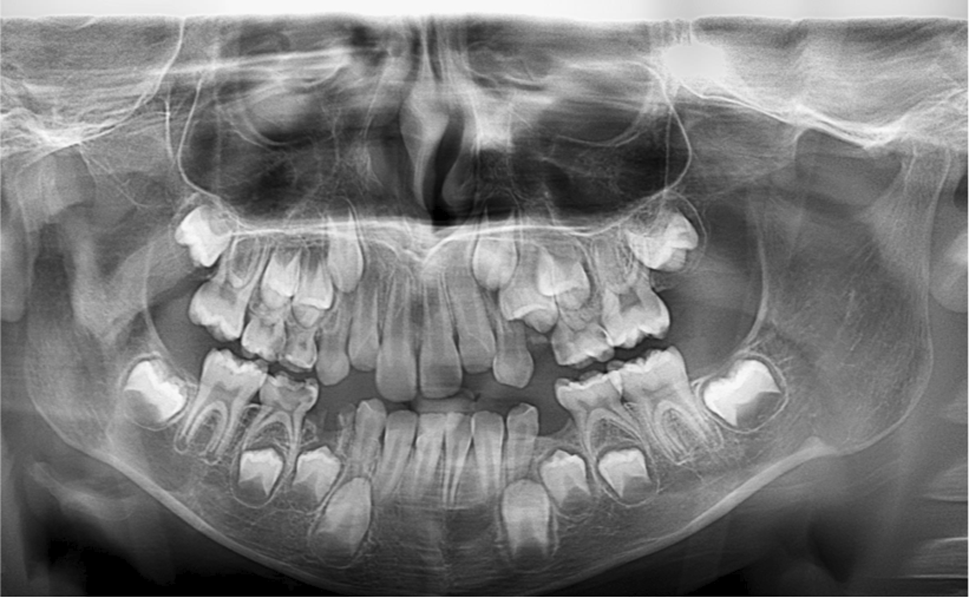

Fig. 1

From: Age estimation using dental and hand-wrist radiography among a sample of Egyptian children

Panoramic image of male patient (Age 8 years and 6 months) Age according to Willem’s method is 8.02 years. Age according to Cameriere’s method is 7.05 years.